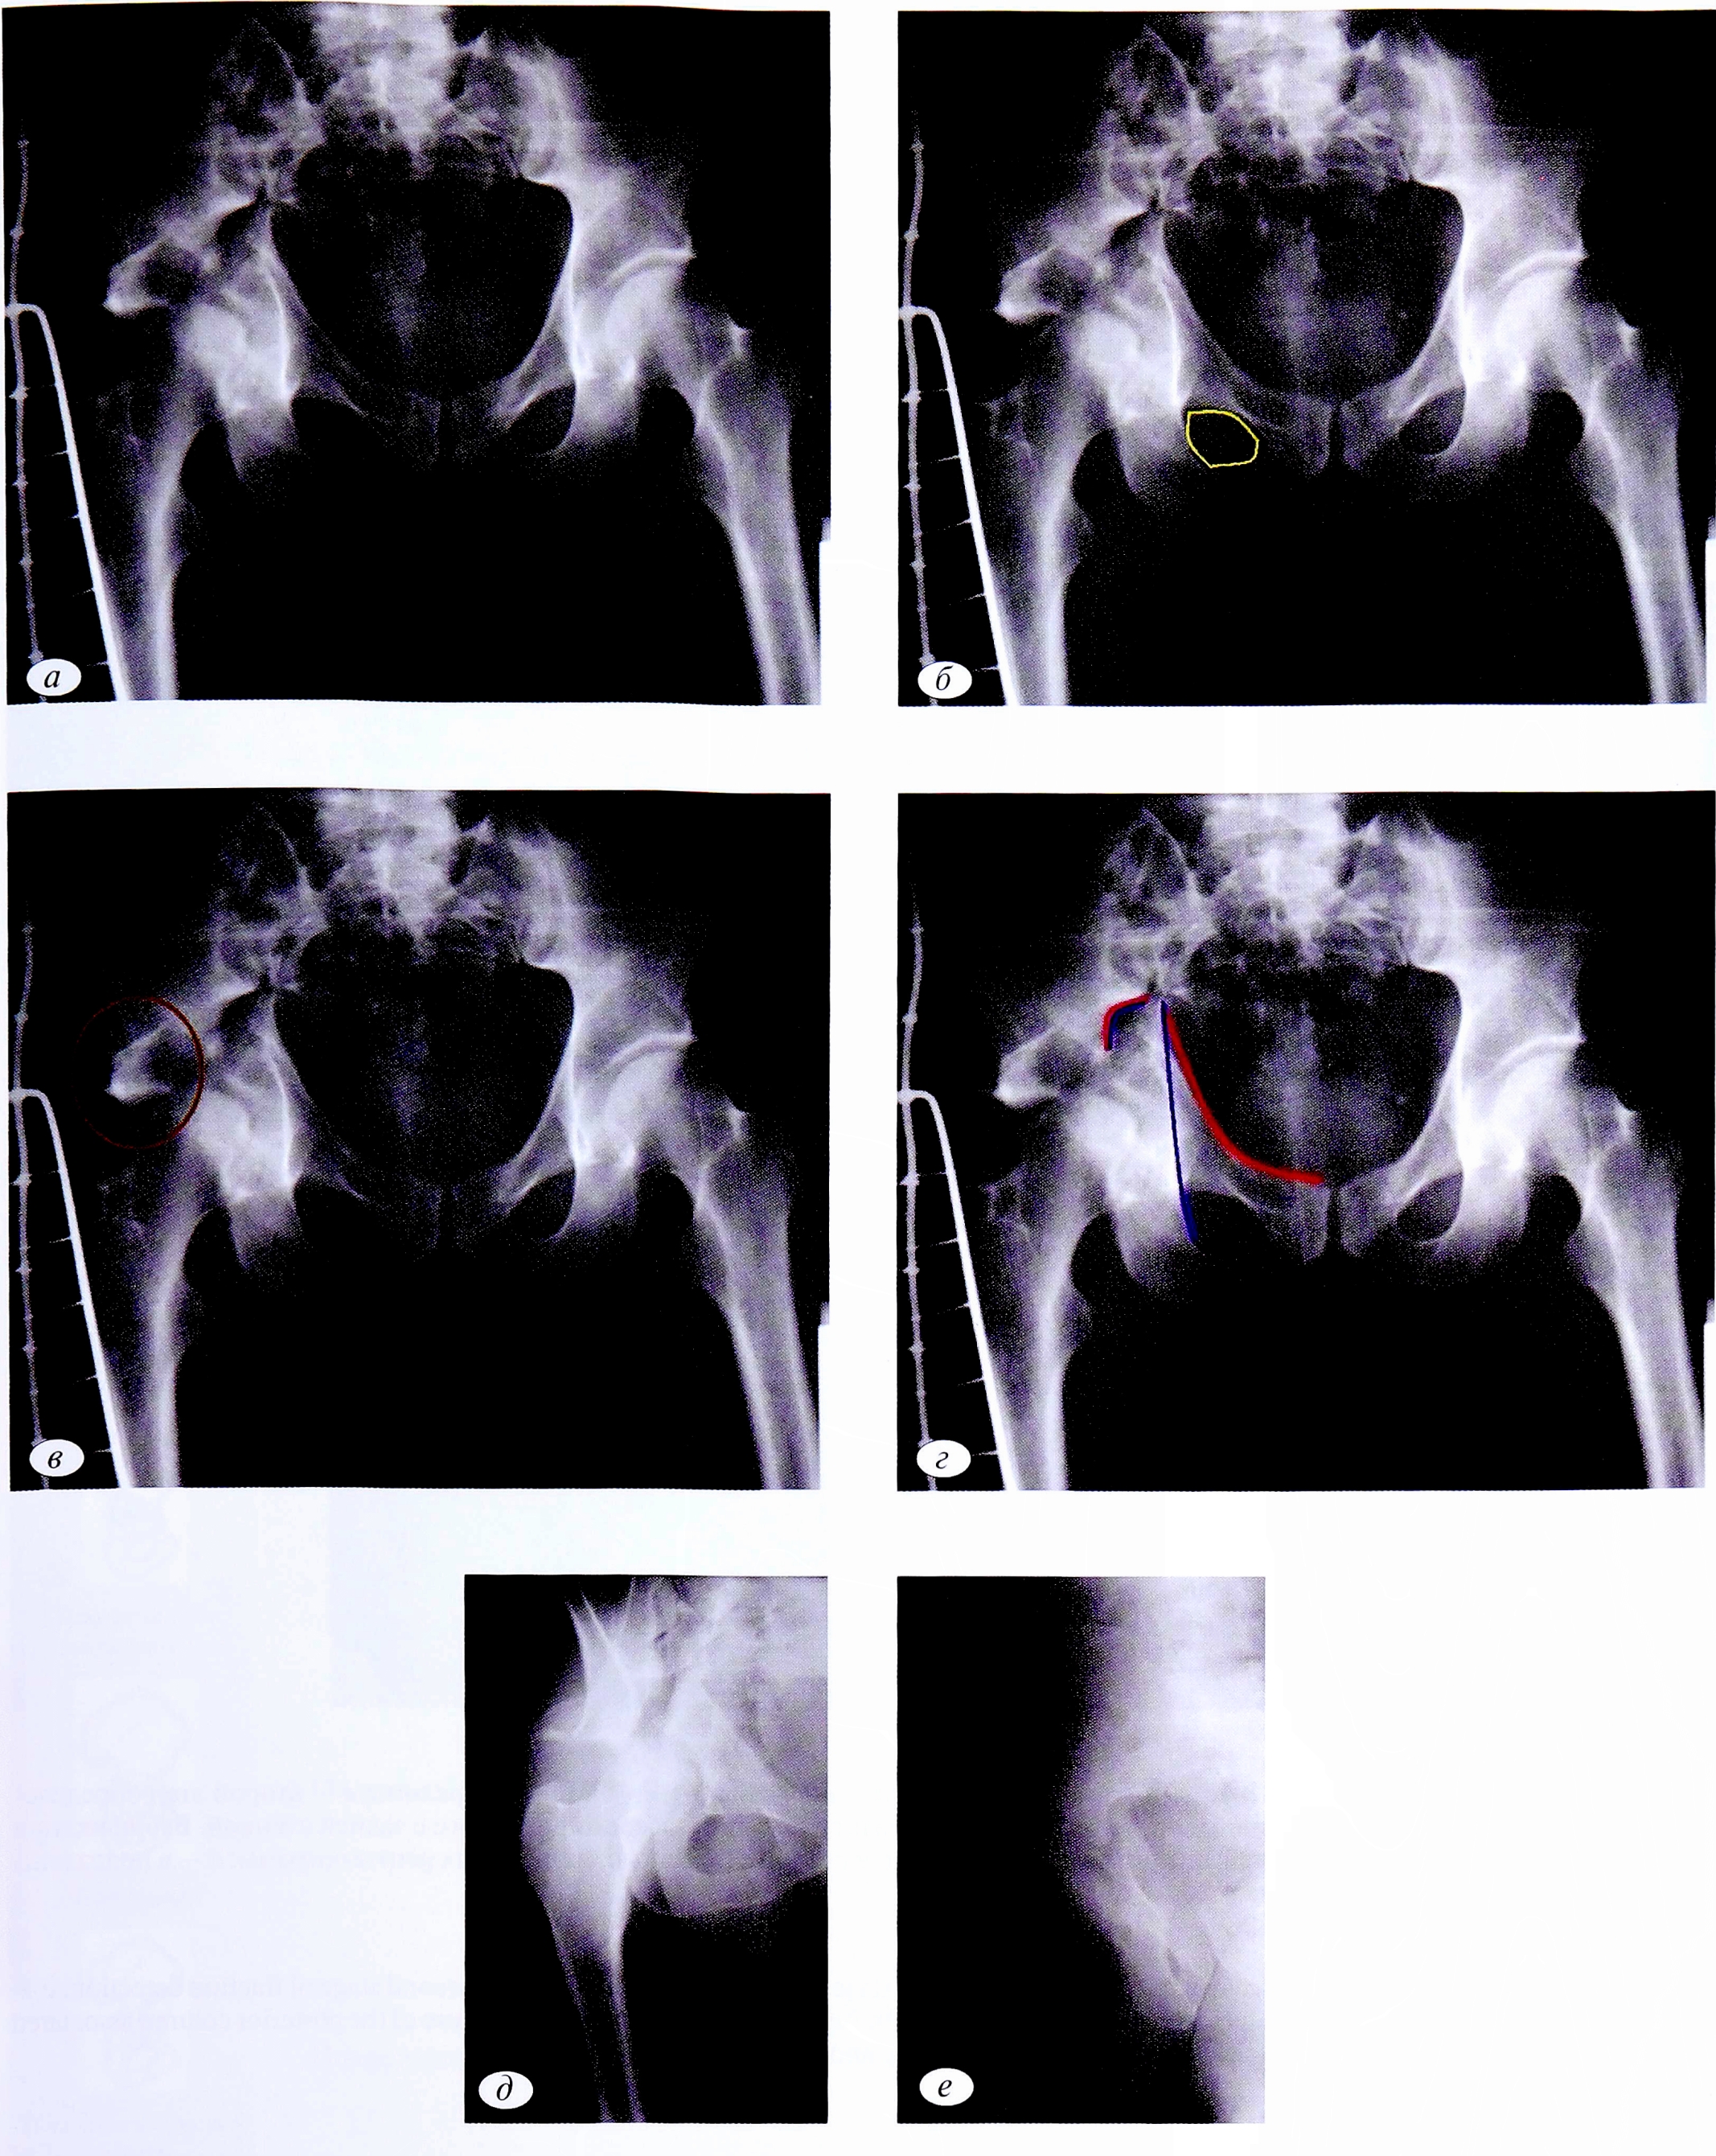

На рентгенограмме в переднезадней проекции (рис. 1, а) определяется целостность подвздошногребешковой линии. Непрерывность линии позволяет исключить переломы, при которых плоскость перелома проходит через терминальную линию (linea terminalis): передняя стенка, передняя колонна, поперечный перелом, поперечный перелом, ассоциированный с переломом задней стенки, Т-образный перелом передней колонны, ассоциированный с задним полу- поперечным, двухколонный перелом (см. рис. 1, б).

Таким образом, уже на первом этапе анализа из 10 возможных ассоциированных переломов вертлужной впадины остается только 3 варианта. При дальнейшем анализе рентгенограммы с учетом нарушенных референтных линий возможно определение топической локализации переломов.

Смещение подвздошно-седалищной линии в сочетании с нарушением целостности контуров запирательного отверстия подтверждает наличие плоскости излома, проходящей через заднюю колонну (см. рис. 1, в). Следовательно, можно исключить 1 из 3 оставшихся типов перелома, а именно — изолированный перелом задней стенки

Затем наличие отдельного фрагмента задней стенки дает возможность исключить изолированный перелом задней колонны (см. рис. 1, г). Таким образом, методом исключения диагностирован перелом задней колонны, ассоциированный с переломом задней стенки.

Объективное подтверждение и характерные детали перелома задней колонны и задней стенки вертлужной впадины были получены на втором этапе лучевой диагностики — при прицельных снимках по Judet— Letournel (см. рис. 1, д, е). На рентгенограмме в косой подвздошной проекции видны смещение задней колонны и неповрежденное крыло подвздошной кости (см. рис. 1, д), в косой запирательной проекции (см. рис. 1, е) определяются отдельный фрагмент задней стенки и целостность подвздошно-гребешковой линии (терминальной линии тазового кольца).

Рис. 1. Пациент №1. а — обзорная рентгенография таза пациента при поступлении; б — первый этап определения перелома; в — второй этап определения перелома; г — окончательное диагностирование перелома задней колонны, ассоциированного с задней стенкой. Верификация перелома задней колонны, ассоциированного с переломом задней стенки с помощью прицельных рентгенограмм: д — в подвздошной и е — запирательной проекциях.

Fig. 1. Patient №1. а — overview X-rays of the patient’s pelvis at admission; б — the first stage of fracture detection; в — the second stage of fracture detection; г — final diagnosis of the fracture of the posterior column associated with the back wall. Verification of the fracture of the posterior column associated with the fracture of the back wall with sighting X-rays: д — in the iliac and e — obturator projection.